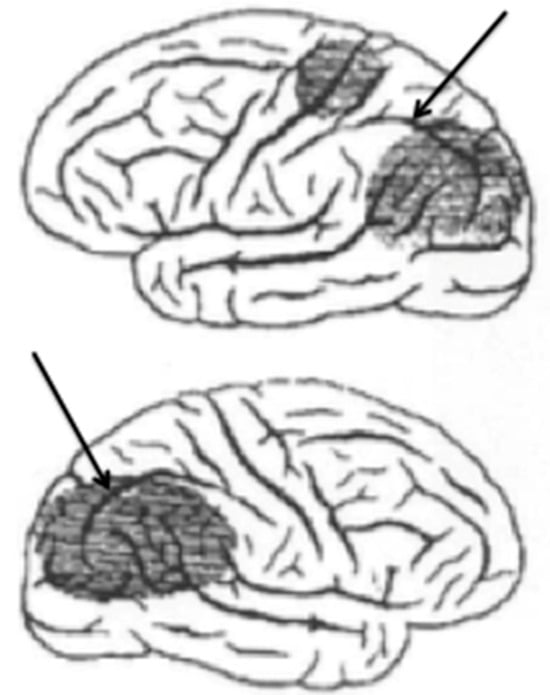

Figure 1 shows an adaptation of a drawing published by Rezso Bálint (1909) showing the regions of both parietal lobes damaged in a patient manifesting a syndrome bearing his name (Husain and Stein 1988). These strokes had damaged the dorsal visual stream bilaterally. Arrows have been added to show the intraparietal sulcus that divides the parietal lobe into the inferior and superior lobules.

The intraparietal cortex, which surrounds the intraparietal sulcus, receives and maintains a retinotopic map of visual information transmitted from the primary visual cortex (Silver et al. 2005). As we shall see, in the intraparietal cortex, these visual signals are integrated with copies of motor commands to move the eyes and upper limbs. Damage to intraparietal cortex causes a bilateral disintegration of these two sources of information and engenders a catastrophic derangement of perception and visually guided behavior that manifests as Bálint’s syndrome.